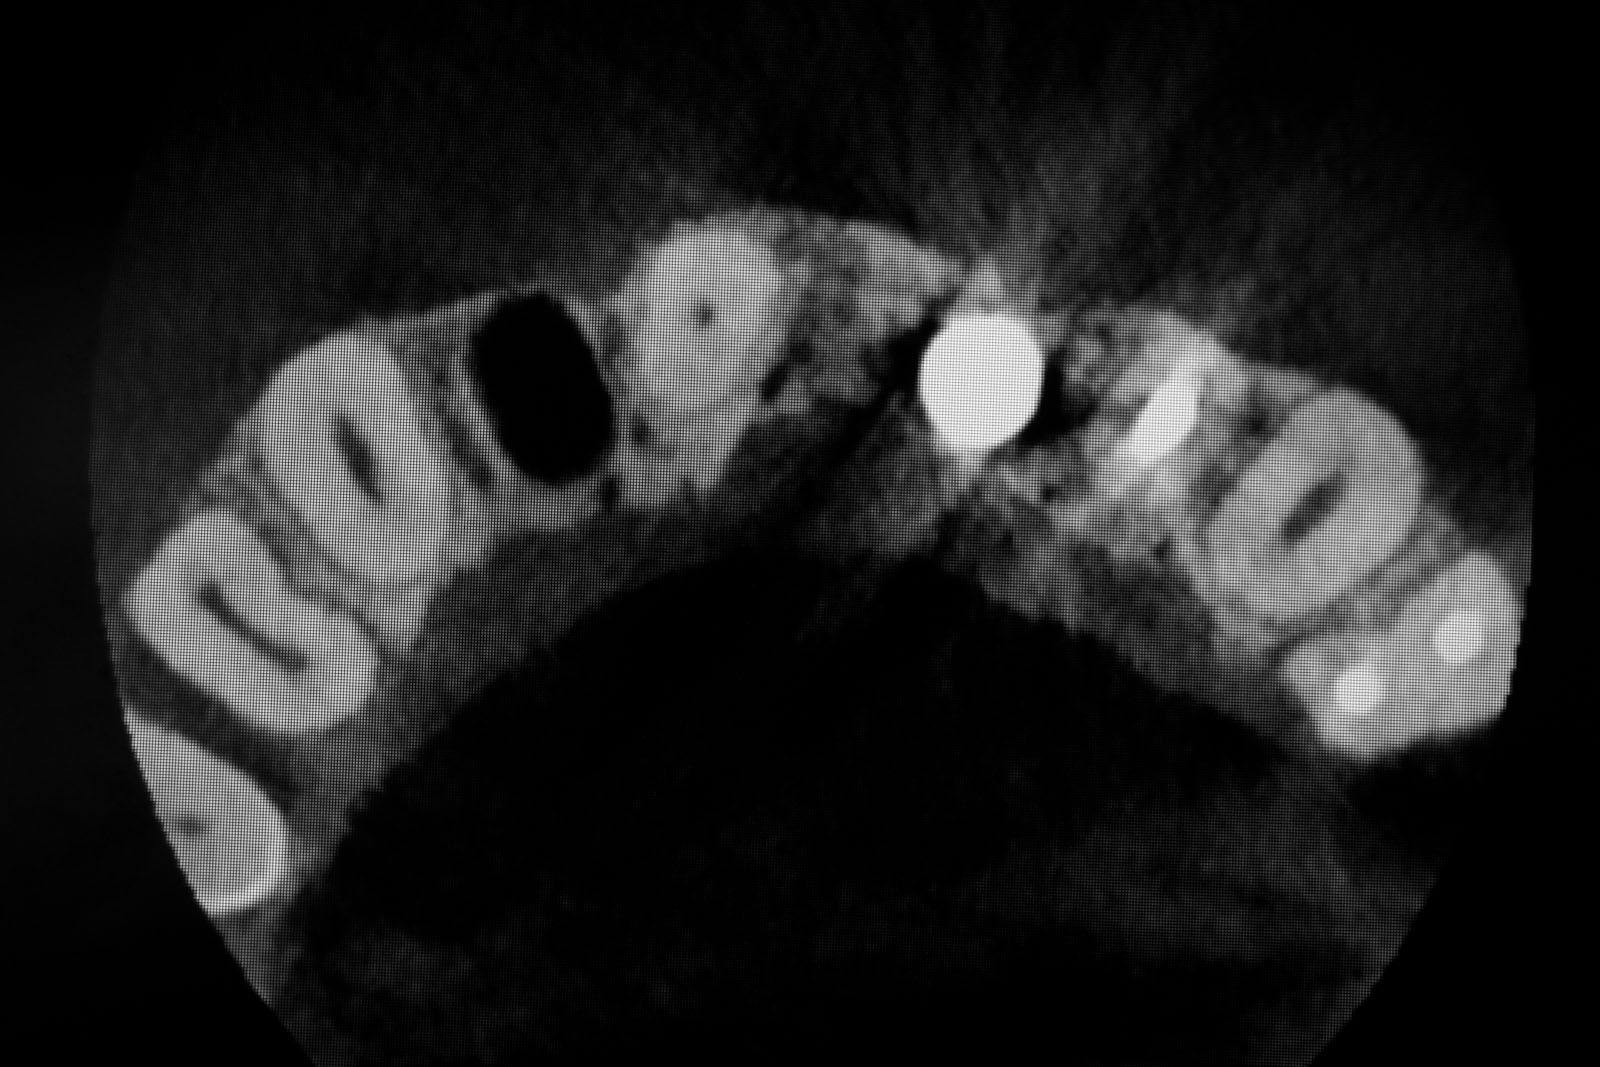

Przed podjęciem leczenia należy określić stopień zaniku kości szczęk oraz żuchwy. W tym celu przeprowadza się badanie kliniczne oraz odpowiednią diagnostykę obrazową pacjenta. Uwzględnia ona zdjęcie panoramiczne OPG jako podstawę dwuwymiarowego obrazowania podłoża kostnego oraz możliwe jest badanie tomograficzne CT lub bardziej precyzyjna tomografia stożkowa CBCT. Opcjonalnie wykorzystywana diagnostycznie tomografia pozwala na bardziej wnikliwą ocenę stopnia zaniku kości w trójwymiarowym, przestrzennym obrazie.